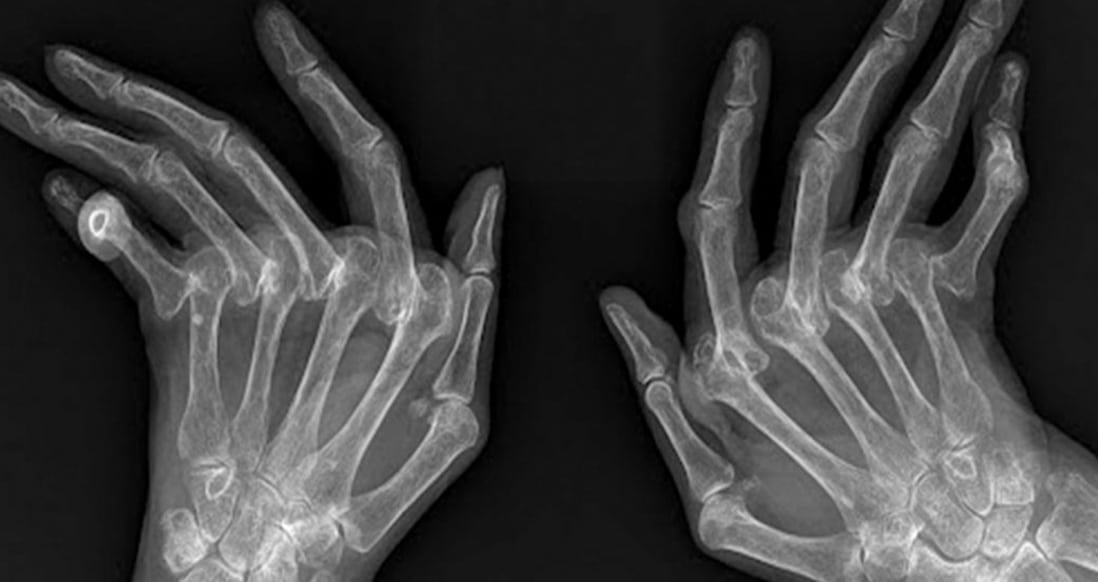

Η ρευματοειδής αρθρίτιδα (ΡΑ) είναι μια αυτοάνοση μορφή αρθρίτιδας που προσβάλλει τον ιστό που περιβάλλει τις αρθρώσεις.

1. Πόνος στις αρθρώσεις: Ο πόνος είναι ένα από τα πρώτα και πιο βασικά συμπτώματα της ΡΑ. Μπορεί να εκδηλωθεί σε οποιαδήποτε άρθρωση του σώματος, όμως συνήθως είναι συμμετρικός στις δύο πλευρές (π.χ. και στους δύο καρπούς ή και στα δύο γόνατα). Σε αρχικό στάδιο, πονούν οι μικρότερες αρθρώσεις, όπως αυτές των δαχτύλων, των καρπών και των αστραγάλων. Ο πόνος μπορεί επίσης να είναι αισθητός στους ώμους, στα ισχία και/ή στα γόνατα.

3. Πρήξιμο: Το πρήξιμο είναι πιο συχνό στους καρπούς ή στις αρθρώσεις των δαχτύλων και πολλές φορές δεν γίνεται εύκολα αντιληπτό από τον γιατρό, όμως δυσκολεύει τον ασθενή να κινηθεί ελεύθερα.